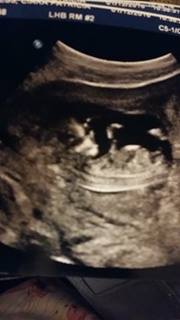

12 weeks 3 days!

Attachment 34114

this is the other one I have

Still think maybe boy, looks a bit like stacking there. But, if the bump is not part of the nub it looks girly. I would say 70/30 for boy from me :)